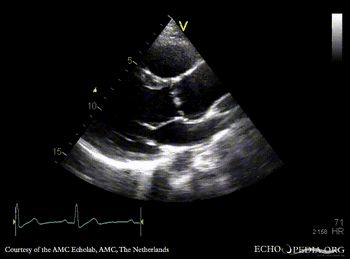

PLAX: dilated aortic root and left ventricle PLAX with Color Doppler: severe aortic regurgitation